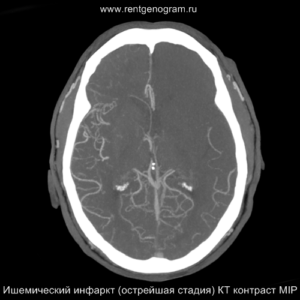

Острая фаза (6 — 24 часа)

В течение острого этапа на МРТ и КТ выявляются все морфологические признаки ишемического инсульта. Область острого ишемического инфаркта визуализируется как зона ↑Т2, ↑Flair, ↑DWI и ↓Т1 ↓ADC. Можно обнаружить тромб в артерии. На КТ в остром этапе также чётко дифференцируется поражённая область, представляющая собой участок с потерей дифференциации мозговых структур и снижением их плотности. Контрастирование в остром периоде не показывает патологических участков с накоплением контраста.

Оценка по шкале ASPECTS

При наличии симптомов ОНМК в первые часы болезни проводилось КТ головного мозга. Для количественной оценки ранних ишемических изменений использовалась шкала ASPECTS (Alberta Stroke Programme Early CT Scale).

Сосудистая зона средней мозговой артерии (СМА) делилась на 10 участков: лентикулярное ядро (L), хвостатое ядро (C), внутренняя капсула (IС), кора островка (I) и 6 зон бассейна СМА – М1, М2, М3, М4, М5, М6. Каждая зона оценивалась в 1 балл (всего 10 баллов). Для оценки учитывались такие проявления, как локальная гиподенсивность мозга. Полное отсутствие изменений на КТ в бассейне СМА соответствовало 10 баллам, в то время как тотальное поражение — 0 баллов.